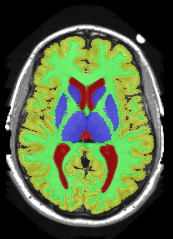

![]() |

| (a) tree and min-margins | ||||

|

Subject 3 |

Subject 4 |

| ground truth | a-exp [7, 8] | QPBO [25, 8] | ours | |

Brain Segmentation:

We combined the labeled regions in dataset [19] (T1W MRI) to create the tree shown in Fig. 15(a). In this setting, the data term is the sum of color model penalty and an shape prior [5] based on an automatically extracted brain mask using [16],

where is the intensity at pixel and is the Euclidean Distance Transform of the extracted brain mask. Min-margins are shown in Fig. 15(a). We also added a Hedgehog prior [13] for the sub-cortical grey-matter to help our energy differentiate between grey-matter and sub-cortical grey-matter.

In this application our method outperformed QPBO in most cases and a-exp in all cases. In fact a-exp always converged to a weak local minima in this setting, see Fig. 15. Based on our experience the quality of a-exp result depends on various factors, e.g. tree complexity, the number of min-margins introduced, the order in which labels are expanded, and the initial solution. For the subjects that QPBO was able to find the global optimal Path-Moves either found the global optimal or a very close solution.